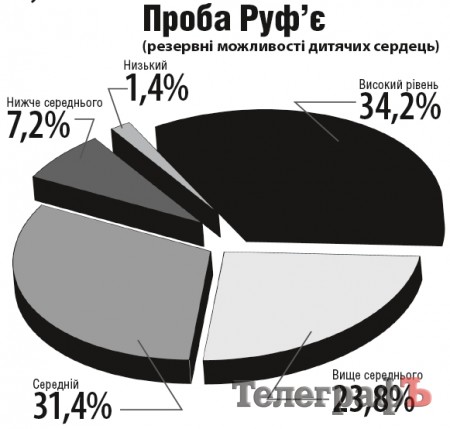

Подведение итогов благотворительной акции «От сердца к сердцу»